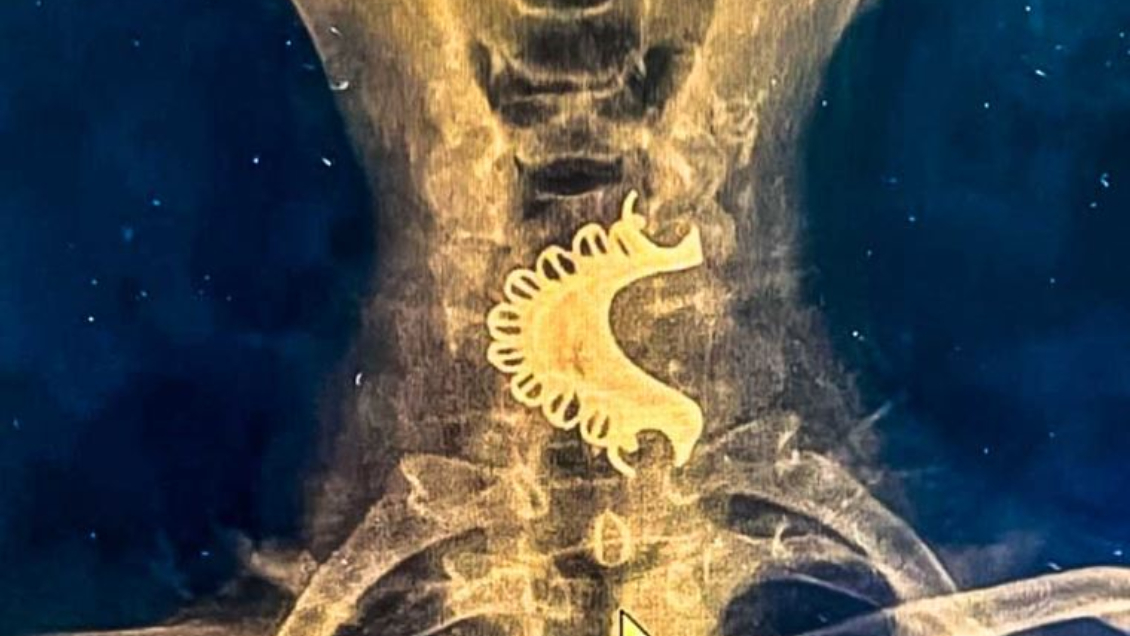

Según dieron a conocer los medios locales, el hombre acudió a un centro asistencial tras presentar dolor y dificultades para respirar. Tras realizarle una radiografía cervical, los médicos descubrieron que la dentadura postiza estaba alojada en la hipofaringe, ubicada en la parte inferior de la garganta, la cual permaneció durante cuatro días ahí.